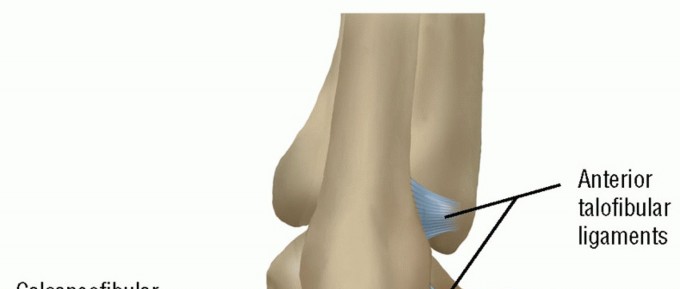

DEFINITION Ankle sprains are the most common athletic-associated in-jury: They represent up to 40% of all spo…

DEFINITION Lateral ankle injuries are among the most common musculoskeletal injuries in the athletic populati…

DEFINITION Lateral ligament instability occurs in some patients after an inversion injury. 38 Although an inv…